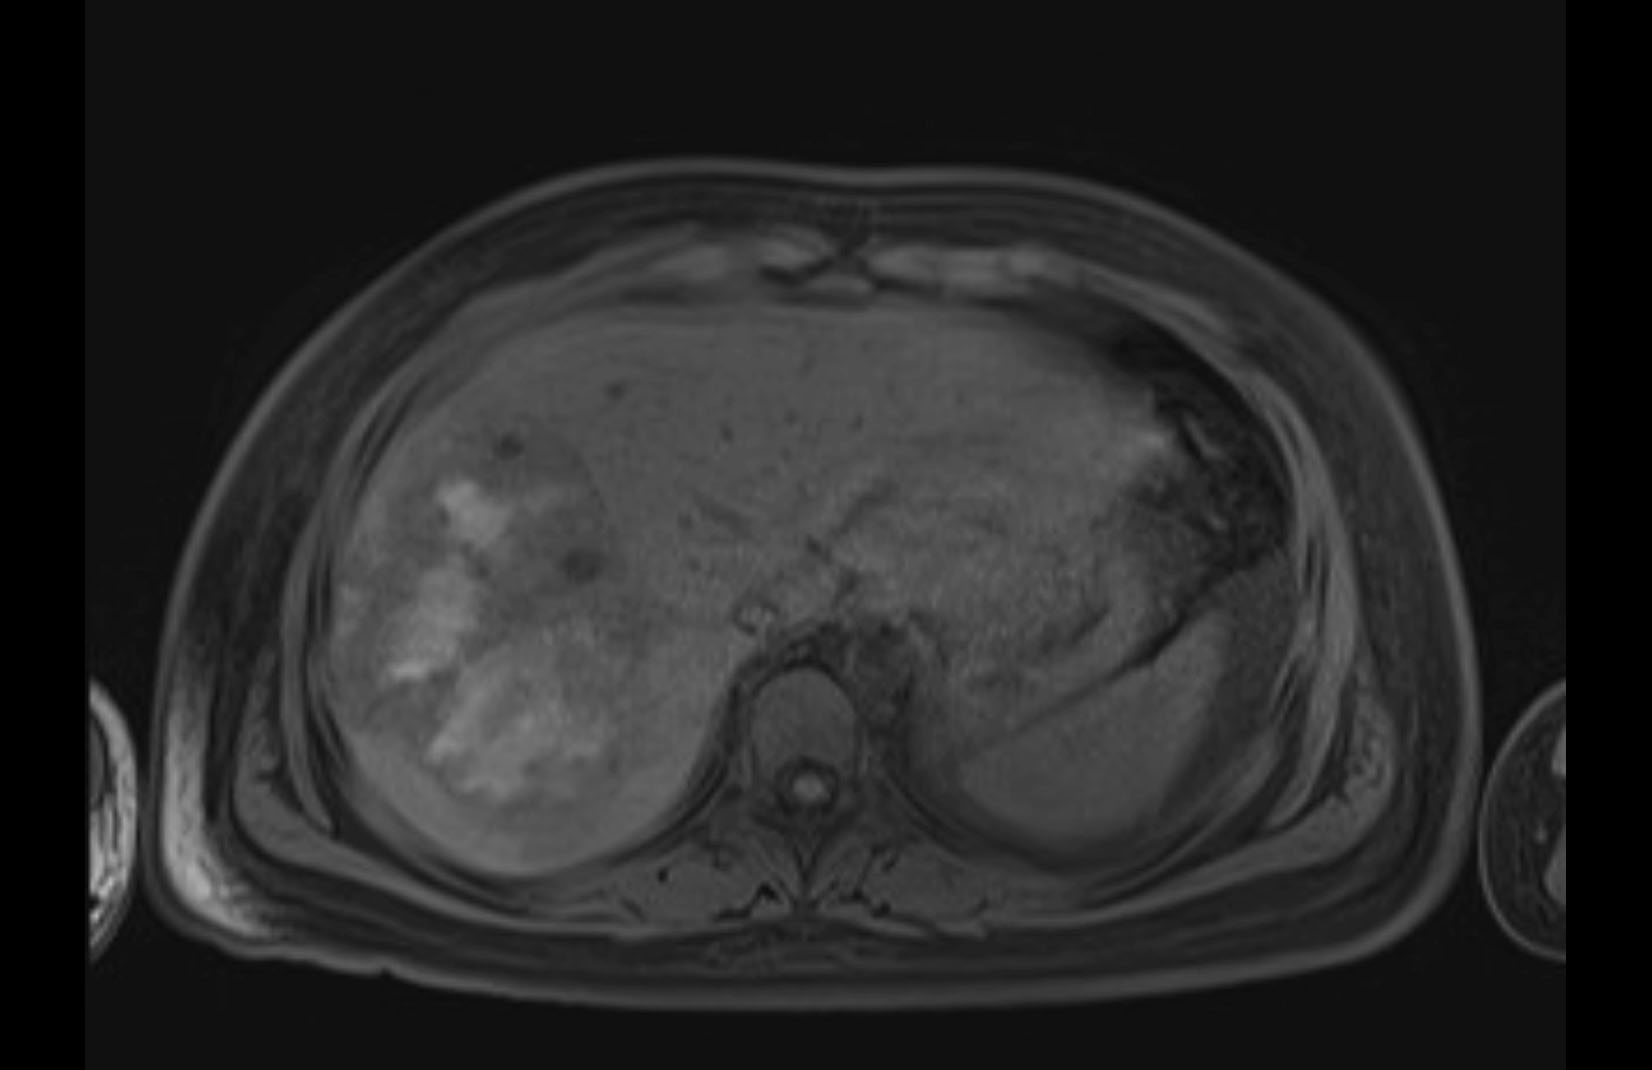

MRI T1

MRI T2